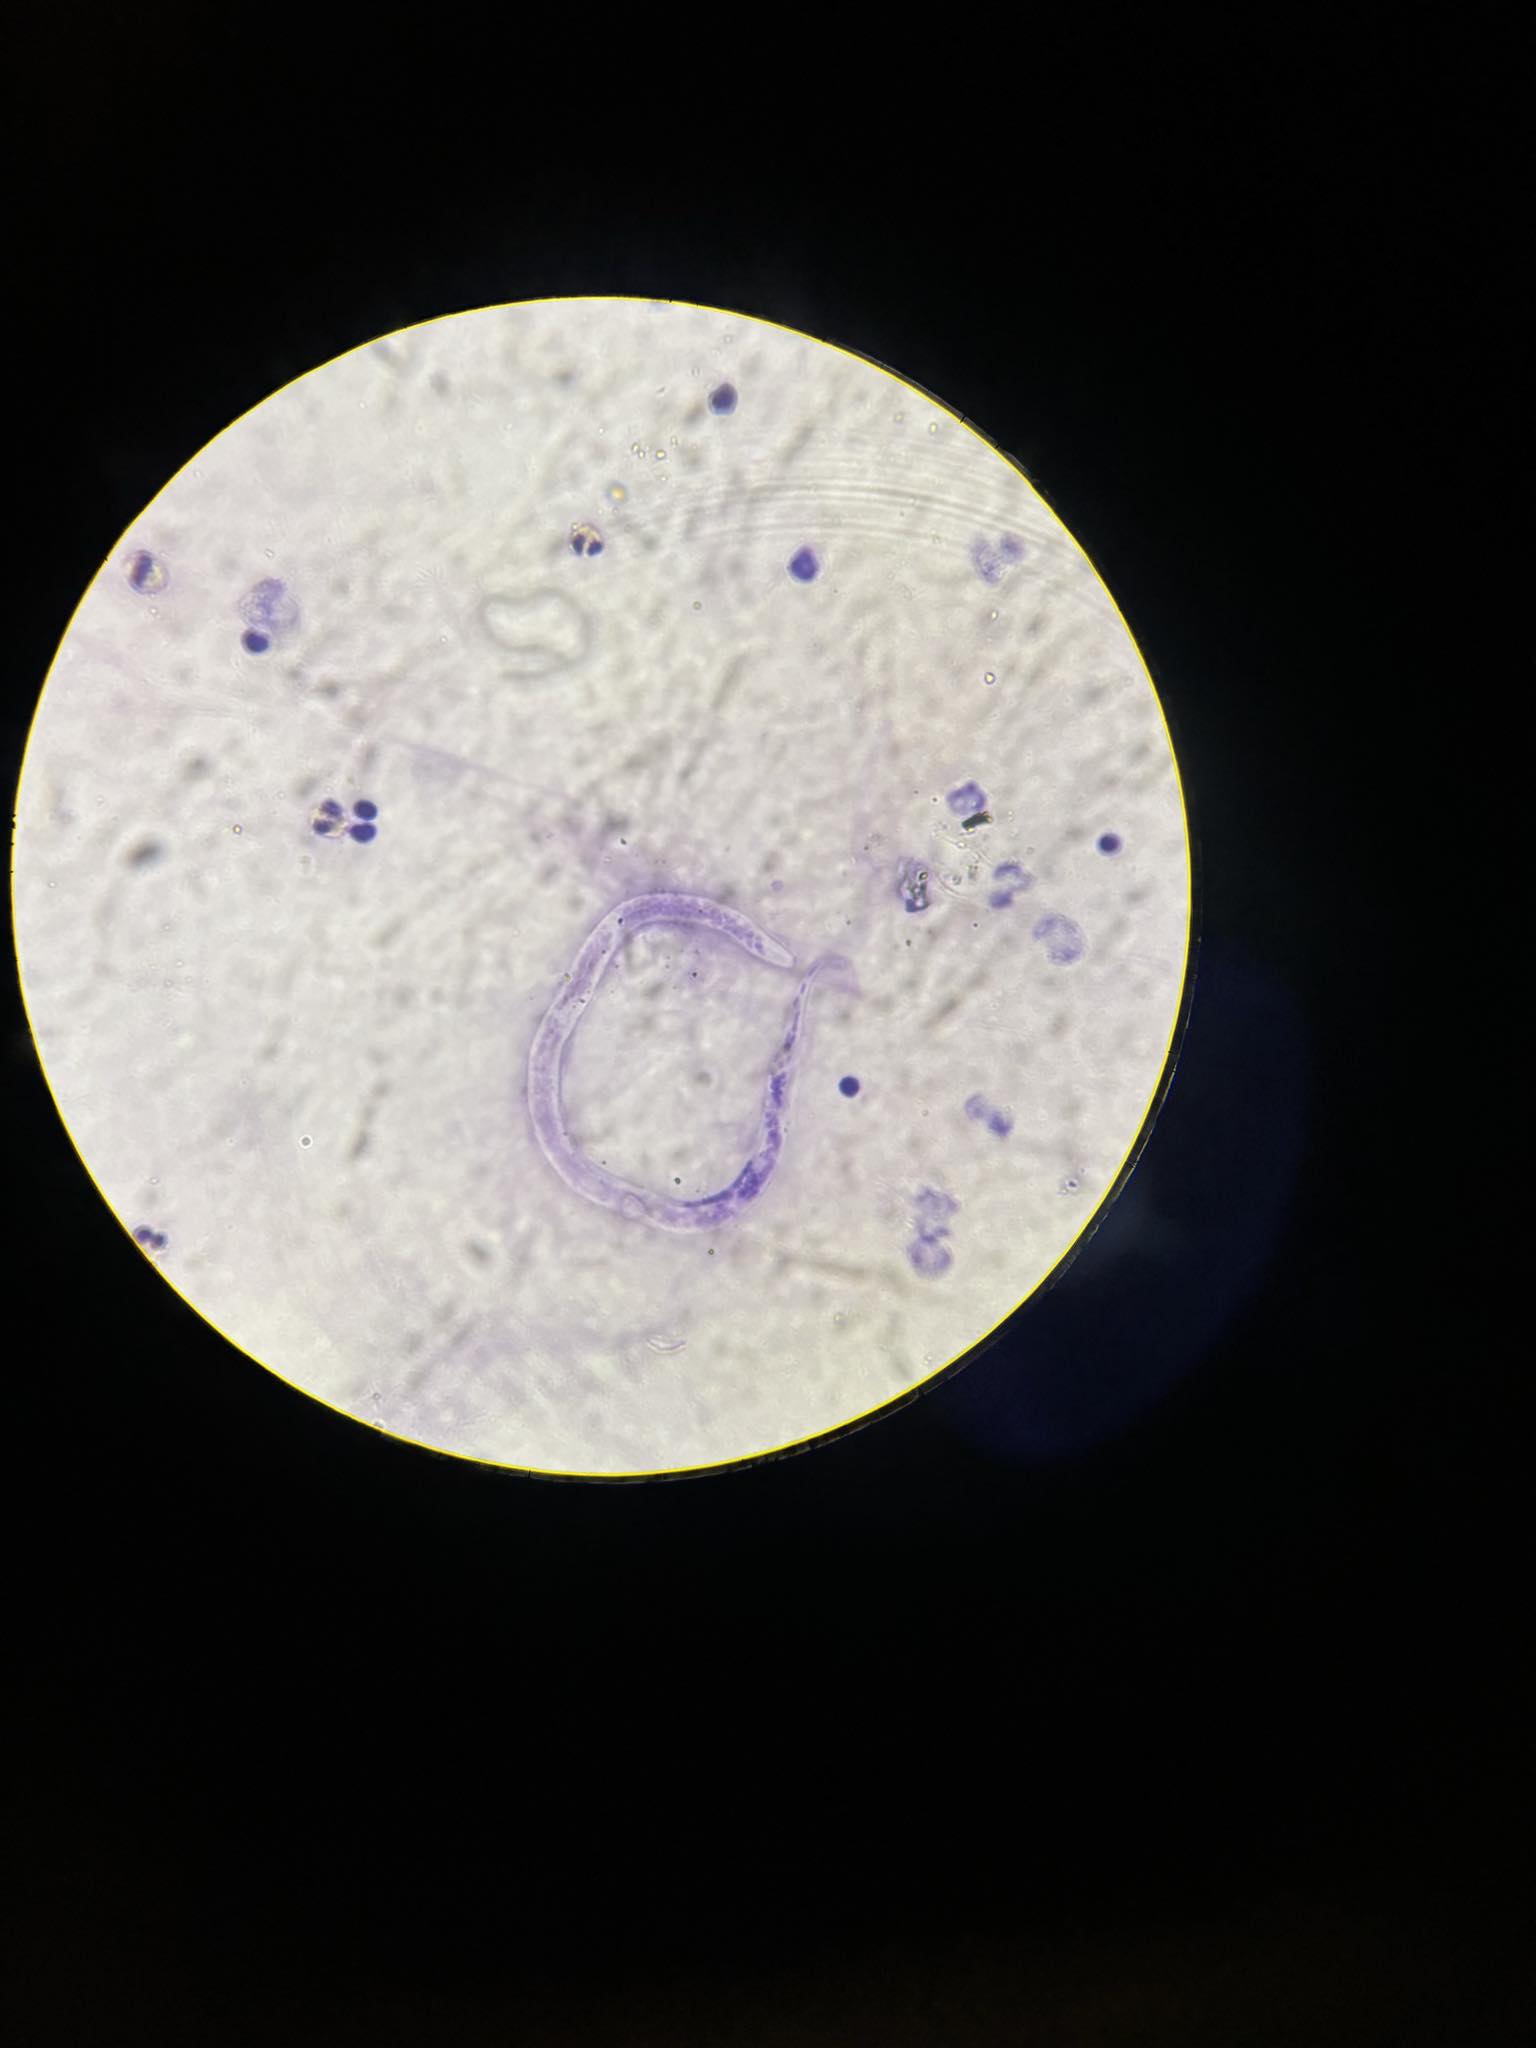

strongyloides stercoralis larwa